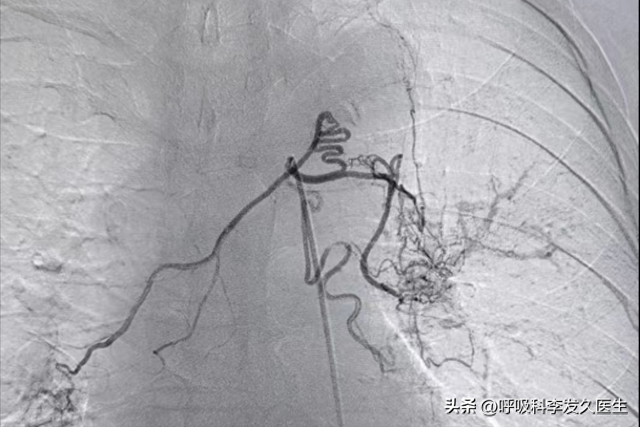

咳嗽痰里有血(咳嗽时痰里带血)

今天想和大家聊一个很多人问过的问题:为什么咳嗽时痰里有血丝?是不是单纯"上火"?很多患者第一次发现痰中带血时,都会紧张地问我:"医生,我这是不是上火了?要不要喝点凉茶?"我接诊过一位45岁的患者,连续三个月把早晨带血...